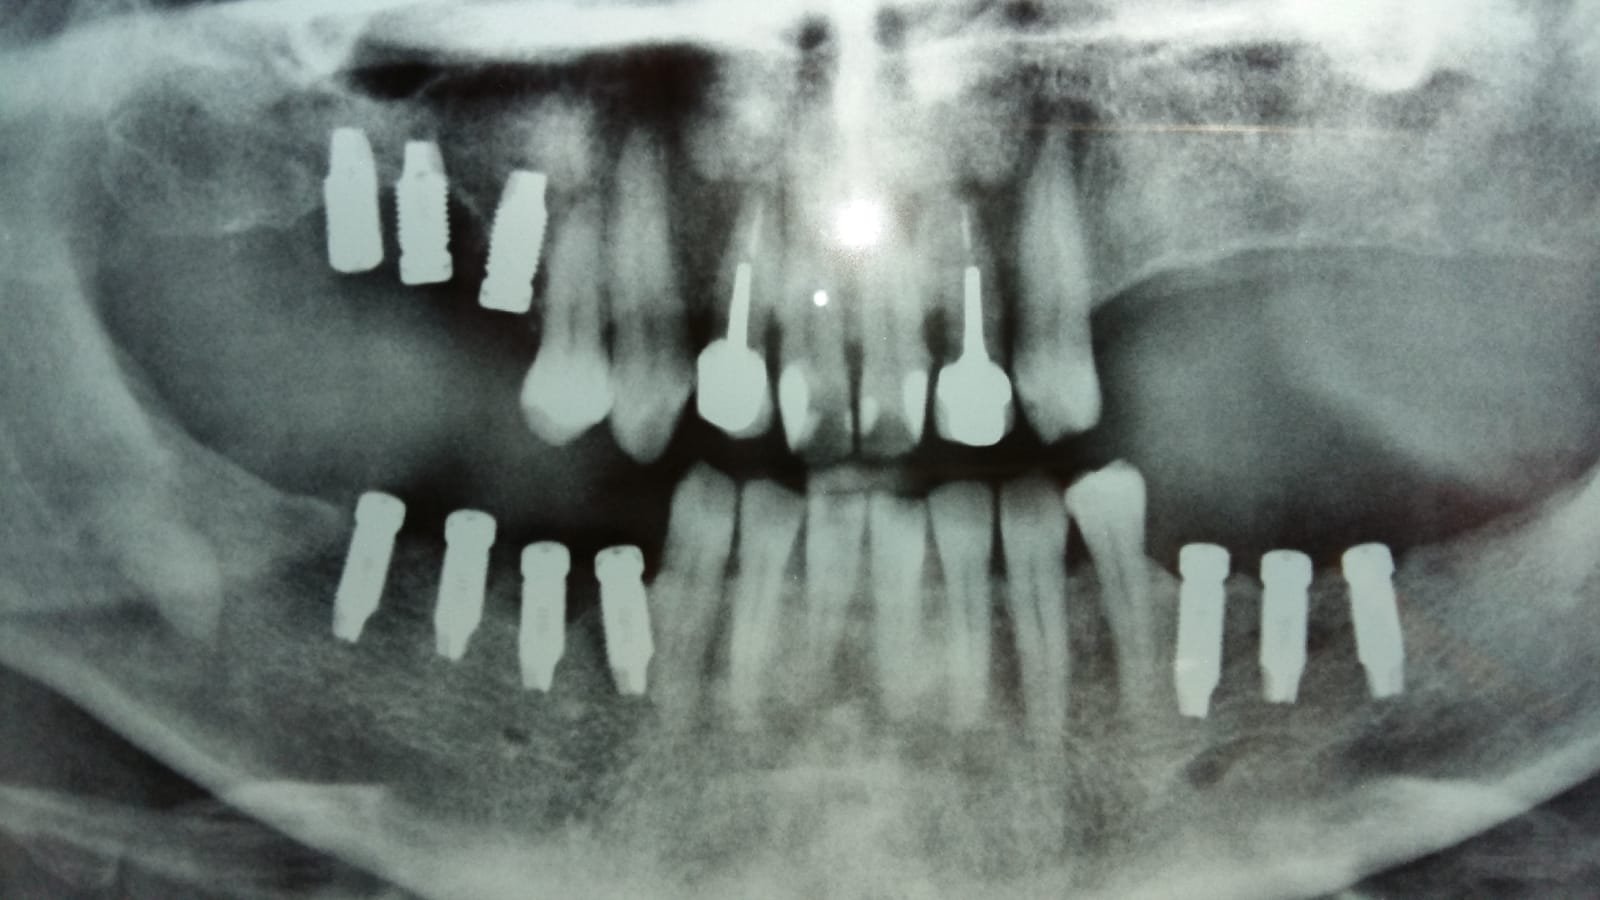

Estos implantes fueron colocados en Bélgica hace 7 años, actualmente lleva una prótesis cementada, agradecería que me pudieran ayudar con la marca de implantes que lleva (lo único que puedo [...]

Buenas tardes. Me pongo en contacto con ustedes para saber su opinión sobre los implantes de este paciente. Son implantes colocados hace muchos años, el paciente tiene 83 años de [...]

Implantes colocados hace alunos años en Vitaldent en una consulta en Barcelona que hoy no existe